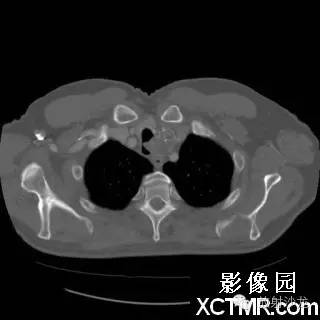

On the contrast-enhanced CT of the chest, there is a heterogeneous mass arising from the left lateral wall of the trachea. The mass demonstrates extratracheal extension as well as extension into the tracheal lumen. (Figure 1 and Figure 2). The mass also contains internal calcifications (arrows), representing chondroid matrix mineralization (Figure 3 and Figure 4).

胸部增强扫描示气管左侧壁发出一不均质的肿块影,肿块向气管内外扩展(图1、2)。其内可见钙化影(箭头),代表软骨基质的钙化(图3、4)。